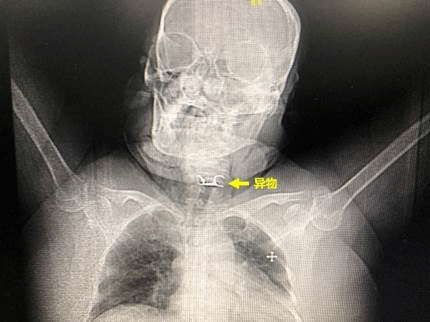

64岁的女性陈某,因误食异物(假牙)后喉部疼痛、呼吸困难,被120急救车紧急送往哈医大一院急诊急救中心。胸外科常浩教授为患者检查发现异物形状特殊、位置刁钻,并且固定假牙的钢钩已刺破食管壁,引起纵隔感染,患者随时面临窒息风险。同时,钢钩毗邻左颈内动脉,随时有刺破颈部血管,导致大出血的风险,患者的生命悬于一线。

在医务科主任李峒作协调下,医院开辟绿色通道,紧急将患者收至外科缓冲病房,并完善相关检查。同时,胸外科常浩教授团队组织消化内科、耳鼻喉科、手术室、麻醉科等多个科室迅速行动,在门诊中心手术室联合制定了完备的手术方案和术中应急预案,随时可以为患者安全快速的取出异物。